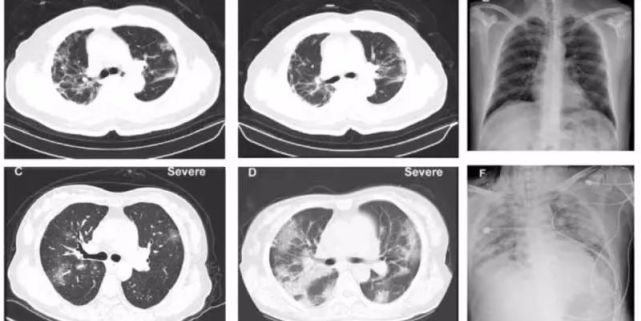

图片新冠肺炎患者的CT影像图,肺部出现毛玻璃样

CT显示,(新冠肺炎患者)肺上出现毛玻璃样。我们要搞清楚是什么导致肺出现毛玻璃样,是水肿?出血?感染?纤维化?里面起反应的是中性白细胞、单核细胞还是淋巴细胞?搞不清楚的话,治疗上就会盲目,一片乱杀。

为什么是这样的?目前还不知道。我们需要在显微镜下去验证,肺的哪个部位病变更明显,是靠近中间,还是外围?具体是什么样的病变,哪一块的炎性细胞比较多?